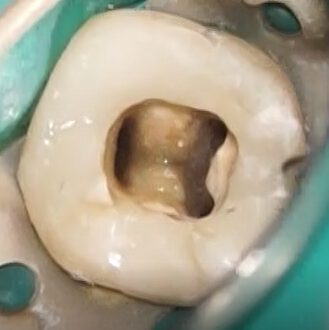

Cleaning

Before and after irrigation. The combination of apical negative pressure, ultrasonic activation, and the new shockwave technology, along with a high irrigant flow rate, resulted in highly effective canal cleaning.